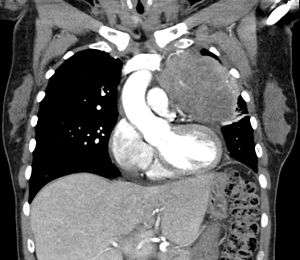

| Thymic carcinoma seen on CT. | |

Thymic carcinoma is a rare type of thymus gland cancer. It usually spreads, has a high risk of recurrence, and has a poor survival rate. Thymic carcinoma is divided into subtypes, depending on the types of cells in which the cancer began. Also called type C thymoma.